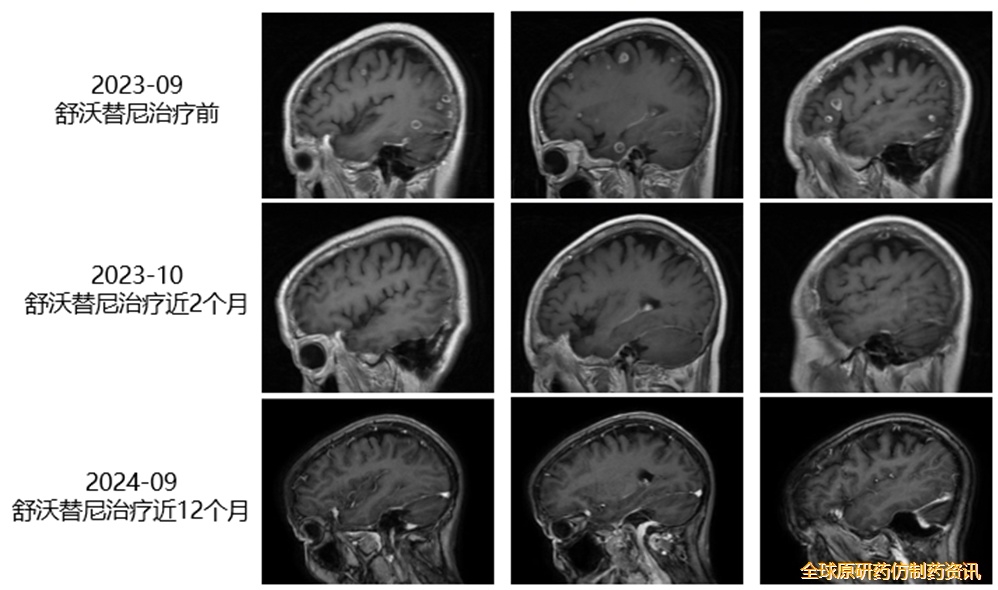

舒沃替尼治疗史:

• NGS检测为EGFR exon20ins突变。

• 2023年9月22日,予以“舒沃替尼(300mg QD)”治疗。复查头颅MRI示病灶缩小,颅内疗效评价为PR(图3),胸部CT增强示肺内病灶大小较前无明显变化(图4)。治疗期间患者仅出现轻度皮疹,整体安全性良好。截至2024年10月末次随访,PFS已超过12个月,持续治疗时间已超过14个月。

图3. 患者接受舒沃替尼治疗前后MRI影像学变化